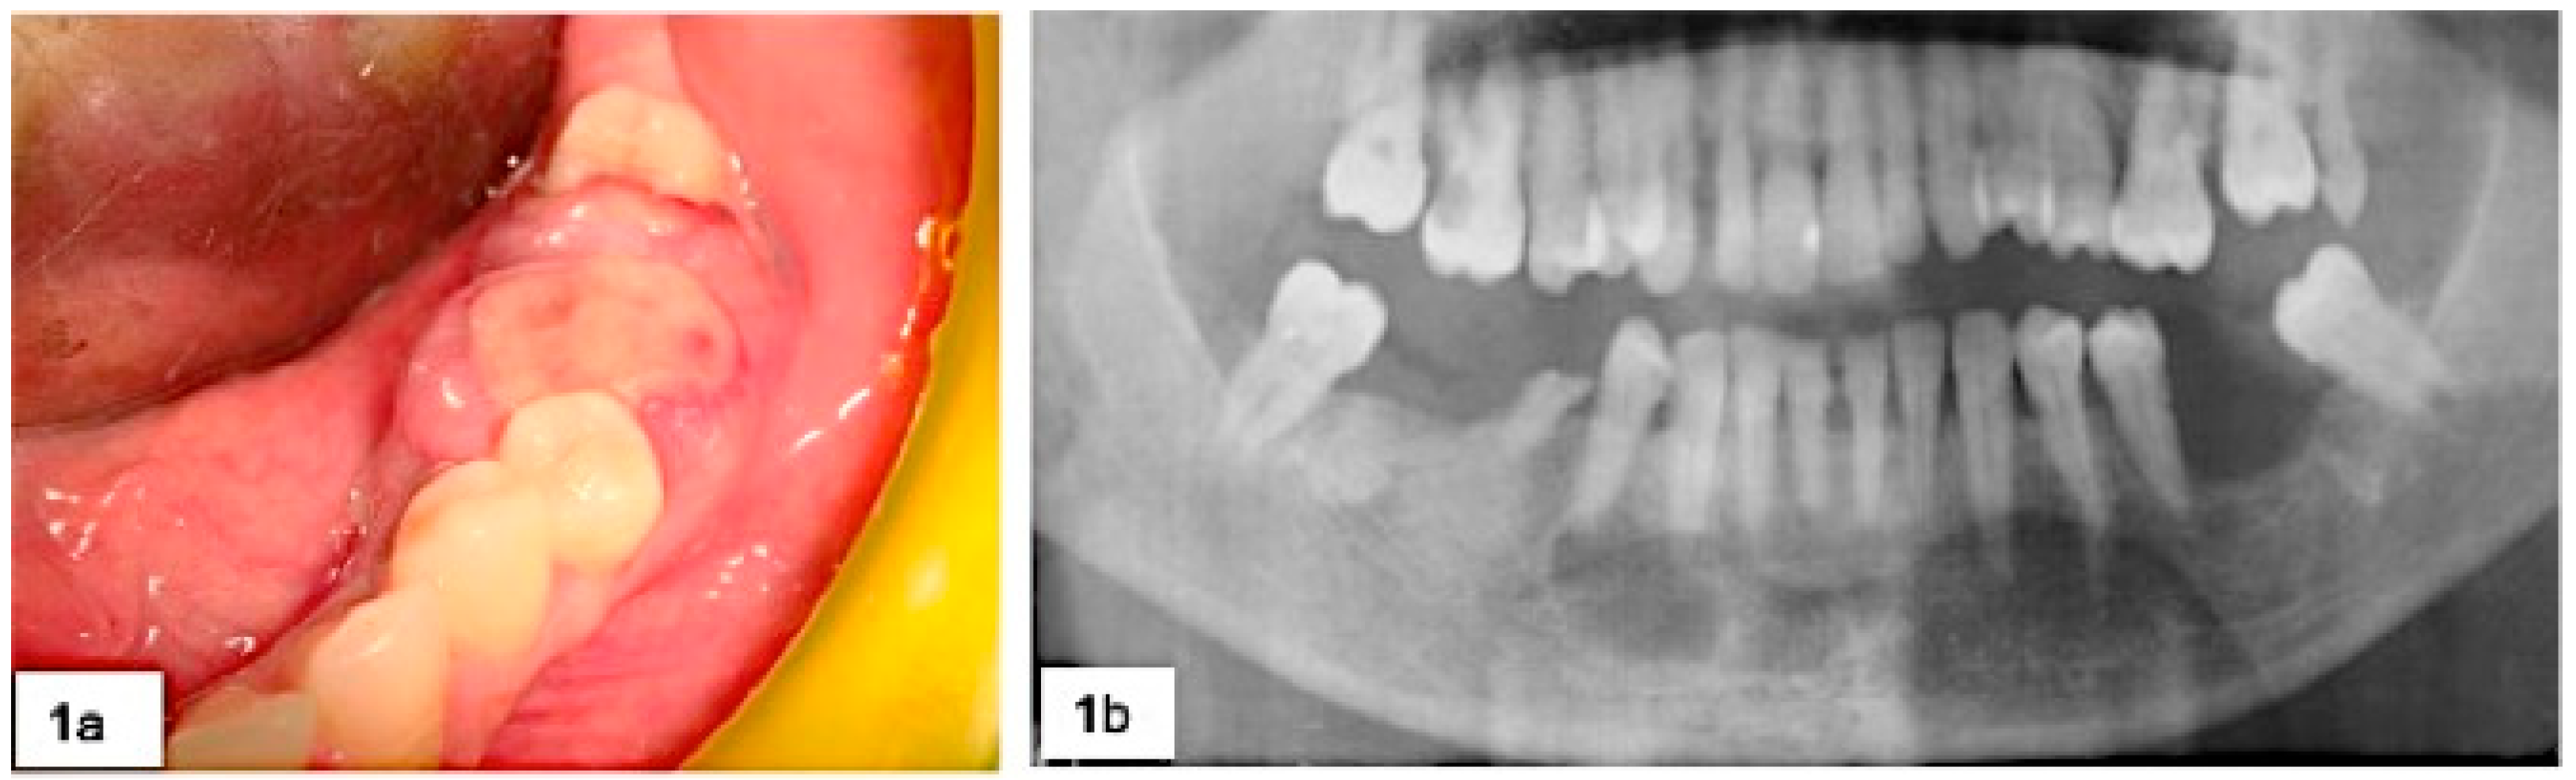

During surgery, in the five cases of severe horizontal bone loss, five teeth and one implant were removed (Figure 2) and abundant bleeding was noticed in 18 cases.

Figure 2. Clinical (a) and radiological (b) follow-up of the patient after 18 months.